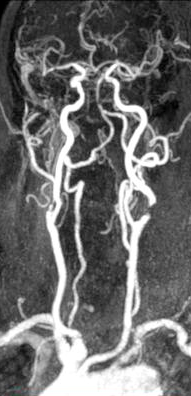

- MRA (Magnetic Resonance Angiografy): een MRI-scan met contrastvloeistof in hals en hoofd

MRA onderzoek